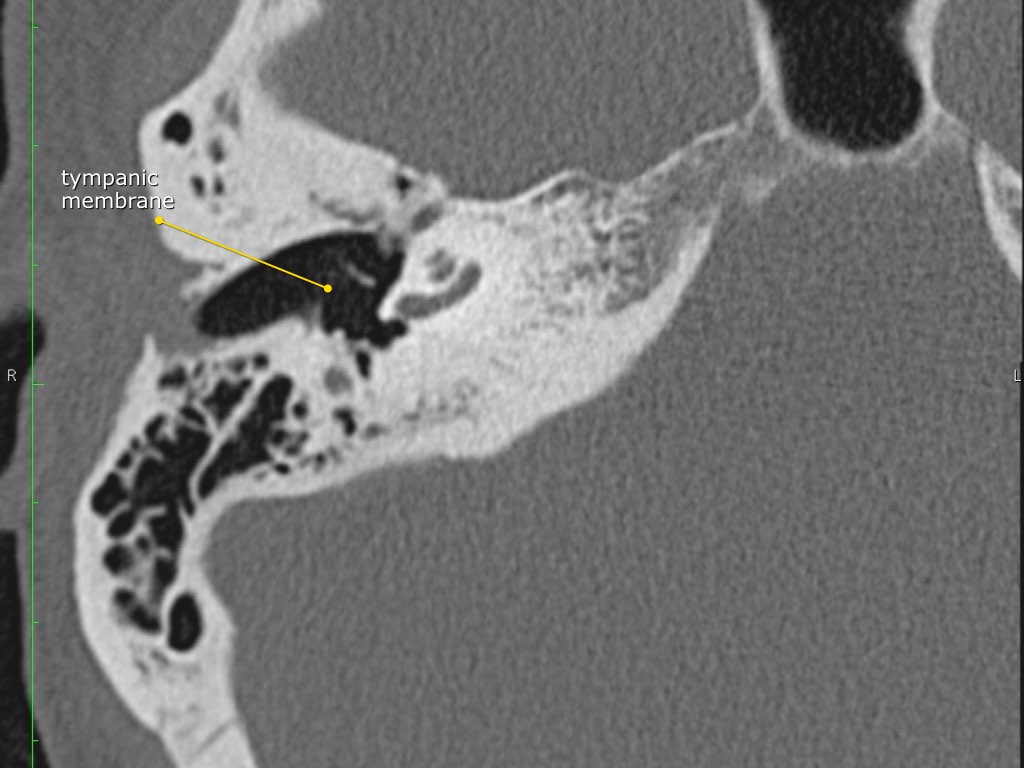

Màng nhĩ

Màng nhĩ hay còn gọi là màng tai, là một màng hình nón ngăn cách tai ngoài với tai giữa.

Pars flaccida là phần trên mỏng manh của màng nhĩ, liên quan đến rối loạn chức năng vòi nhĩ và cholesteatoma.

Pars tensa có kích thước lớn hơn và chắc hơn, thường liên quan đến các trường hợp thủng màng nhĩ.

Cán búa (manubrium) của xương búa được gắn vào phần trung tâm của màng nhĩ, vùng này được gọi là rốn nhĩ (umbo).